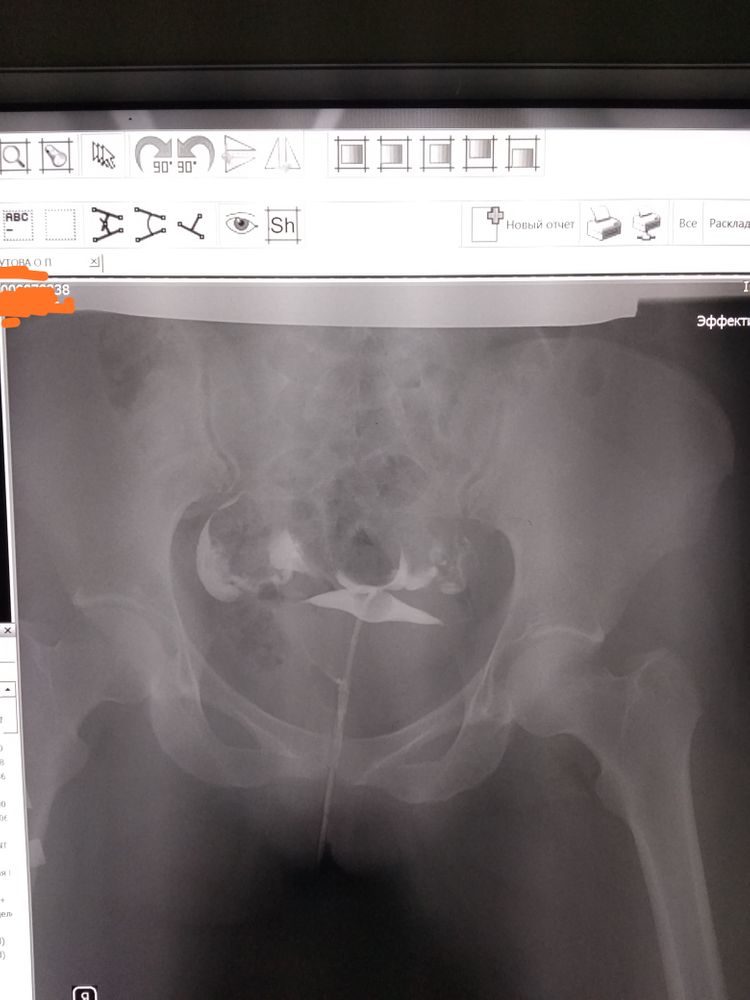

Изображение